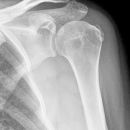

Subcapitale Fraktur und Tuberculum majus